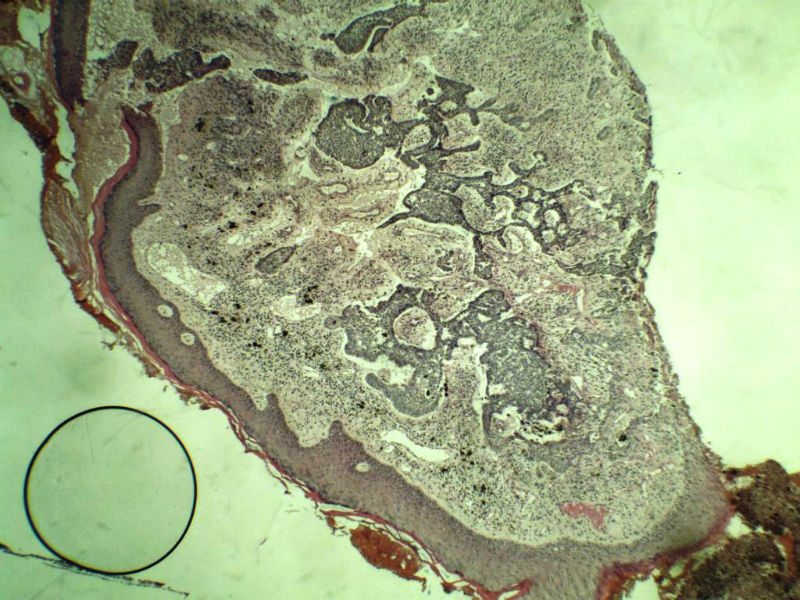

女 67岁 临床考虑面部色素痣 1*0.8 cm  请问各位老师 这是什么? 谢谢!面部包块图1

毛母/发细胞瘤鉴别基底细胞癌,可做CD10,CK7,CK20鉴别

考虑毛发上皮瘤,需除外基底细胞癌。

毛发上皮瘤,需与基底细胞癌鉴别

第一例:毛发上皮瘤

第一例:毛发上皮瘤,与基底细胞瘤区别明显。

第一例  毛发上皮瘤,和基底细胞癌鉴别一下

第一例考虑毛母细胞瘤,第二例考虑基底细胞癌。

毛母细胞瘤

第一例:毛母细胞瘤;第二例:基底细胞癌

第一例,毛发上皮瘤;第二例,基底细胞癌。

一毛发上皮瘤